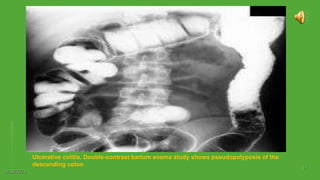

Ulcerative colitis. Double-contrast barium enema study shows pseudopolyposis of the

descending colon

10/29/2023 11 Ulcerative colitis. Double-contrastbarium enema study shows pseudopolyposis of the descending colon